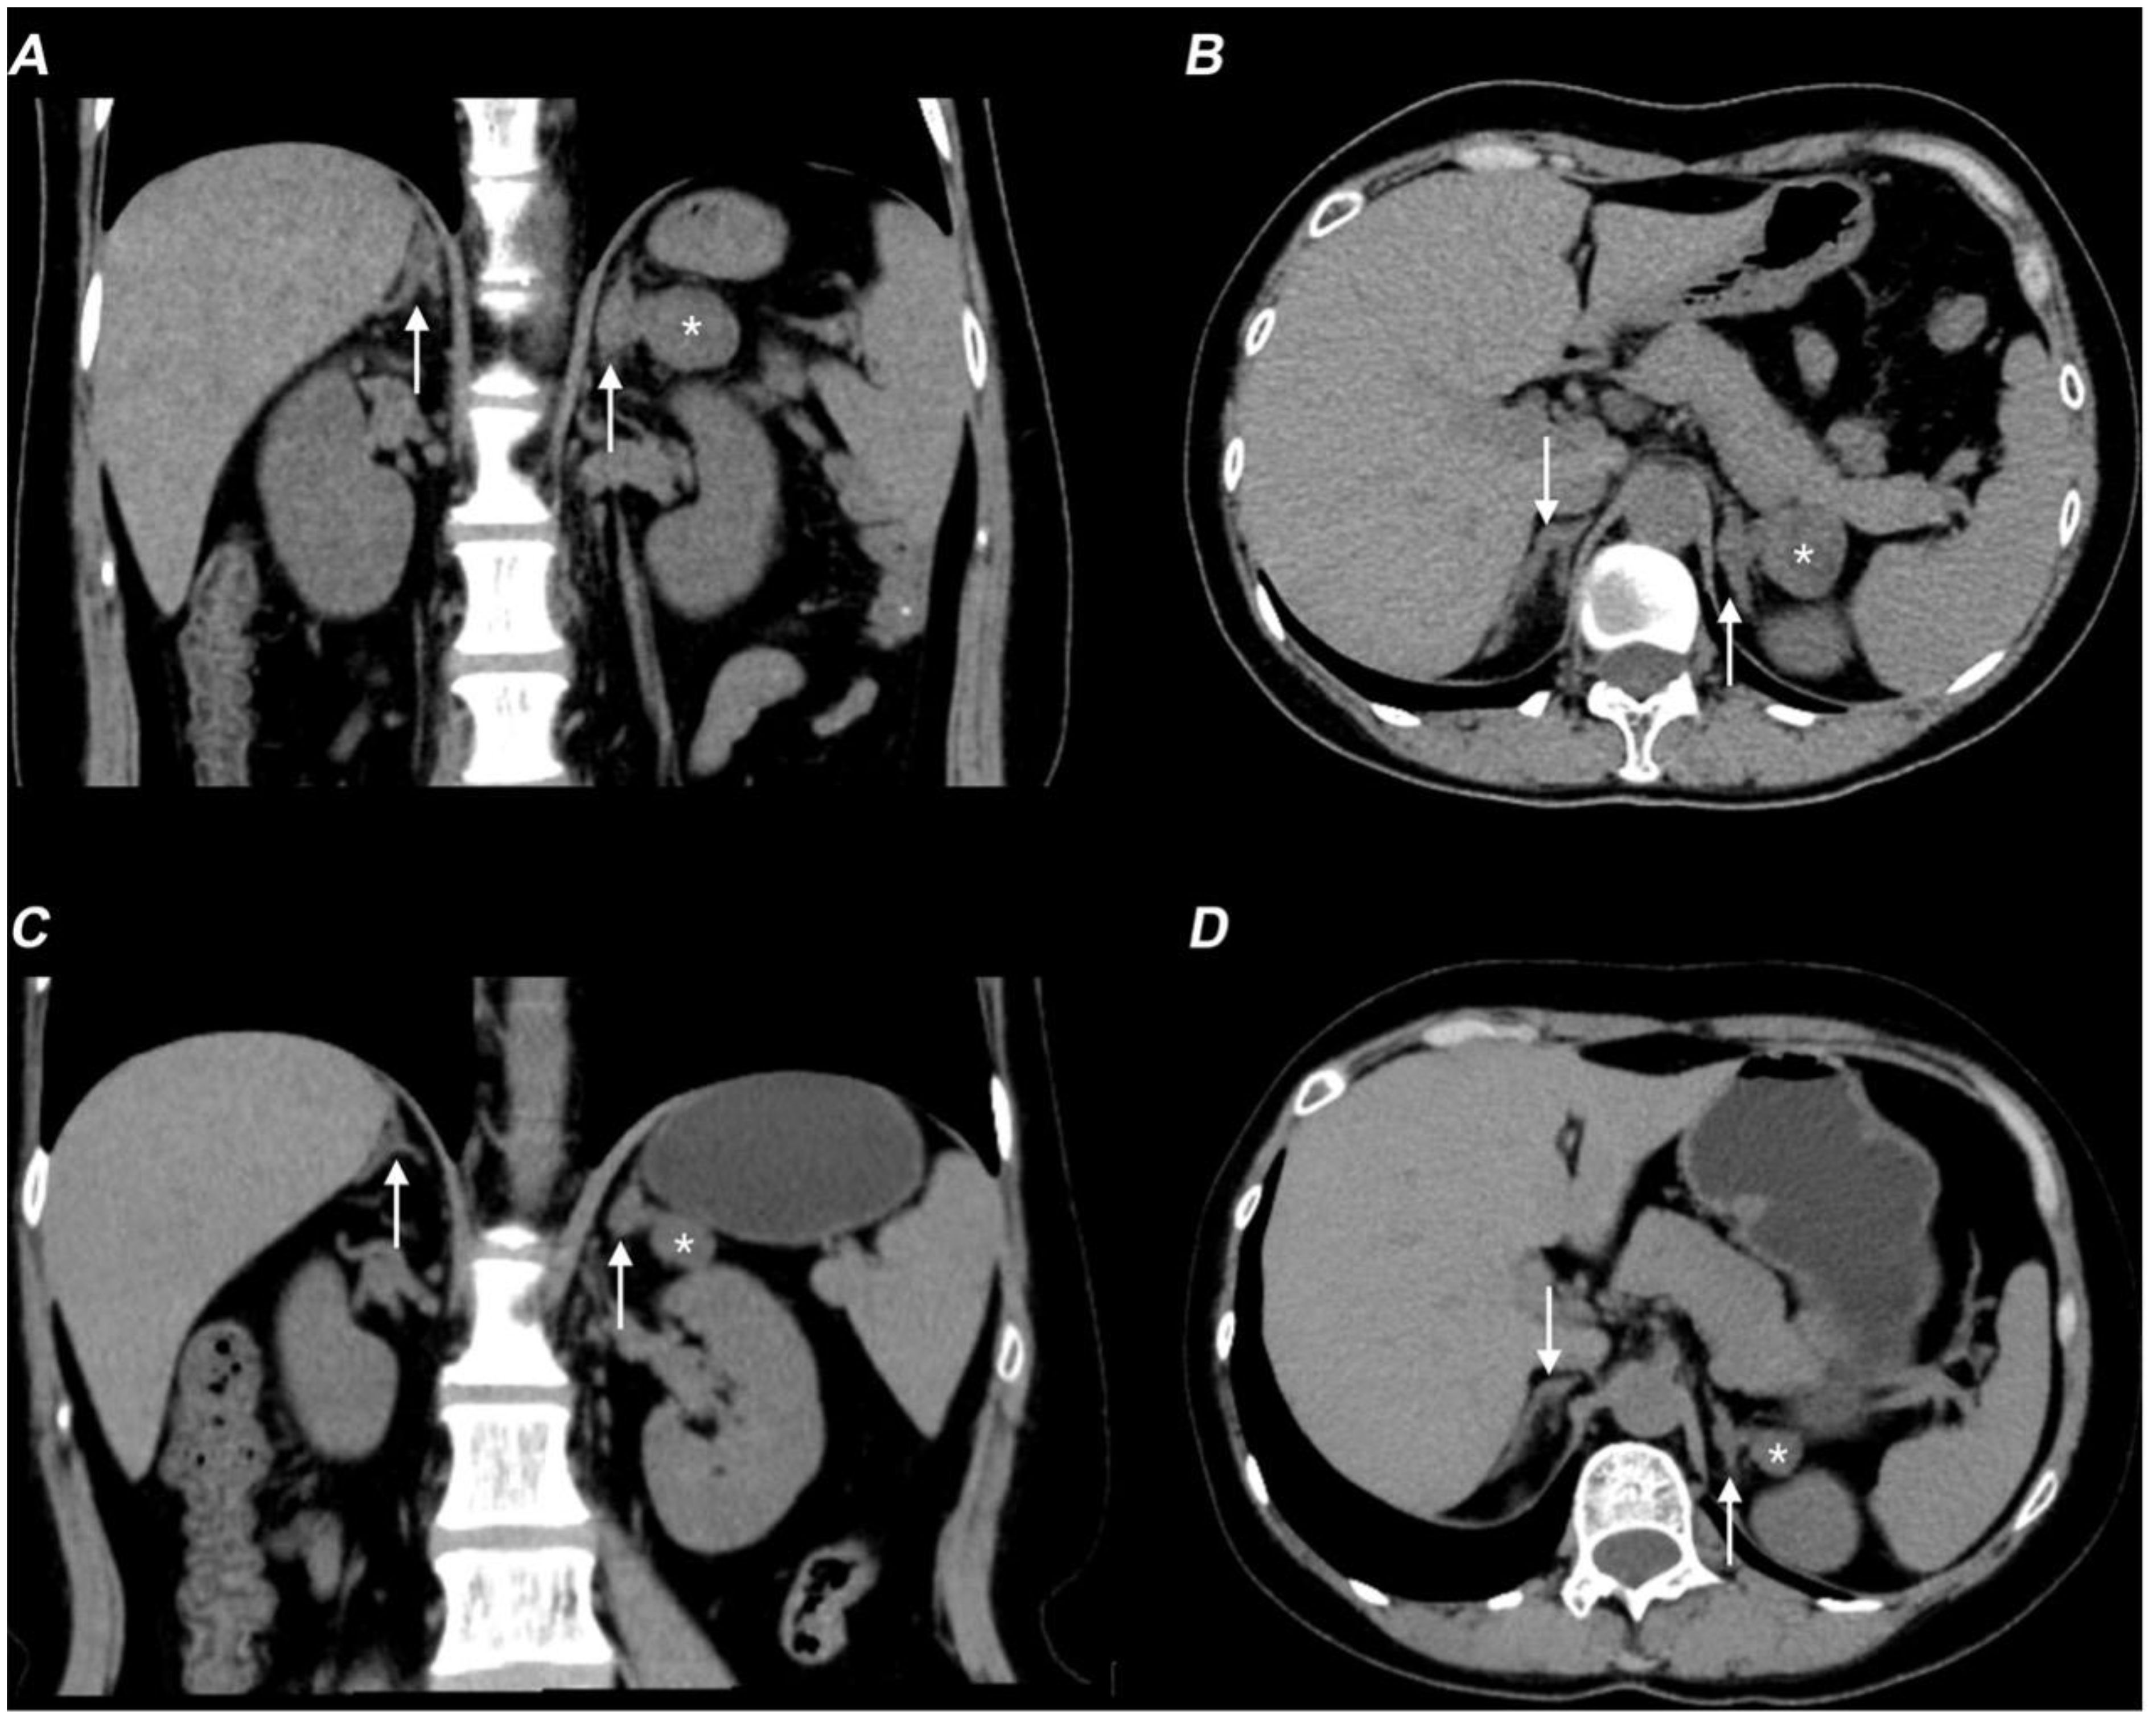

Hormonal profiling (Table 1) showed hypogonadism (low estradiol [21 ng/L] and testosterone [<0.10 ng/mL]), with elevated gonadotropins (FSH 11.36 mIU/mL, LH 17.96 mIU/mL), and adrenal insufficiency (cortisol 79 nmol/L with ACTH elevation [96.3 pg/mL]). She also exhibited hypokalemia, low aldosterone levels, and decreased renin activity. CT showed a left adrenal mass and right adrenal hypertrophy (Figures 2A, B), while ultrasound detected enlarged multi-cystic ovaries.

Figure 2. Non-contrast CT scan showing therapy-related adrenal changes in the patient with 17-OHD. (A, B) Axial (A) and coronal (B) non-contrast CT images show bilaterally enlarged adrenal glands (arrows) and a lesion (*) in the adrenal gland before therapy. (C, D) Axial (C) and coronal (D) non-contrast CT images show improvement in bilateral adrenal gland thickening (arrows) and a decrease in the size of the left adrenal mass (*).

Following treatment with hydrocortisone (10 mg once daily), dexamethasone (tapered from 0.375 mg daily to 0.375 mg every other day), spironolactone (20 mg twice daily), and estradiol-dydrogesterone, the patient achieved normalization of blood pressure and electrolyte levels, restoration of hormonal balance, and significant reduction in both ovarian cysts and adrenal hyperplasia (Figures 2C, D). Remarkably, follow-up breast MRI at six months demonstrated significant reduction in both mammary duct ectasia and the number/size of nodules (Figures 1D–F).